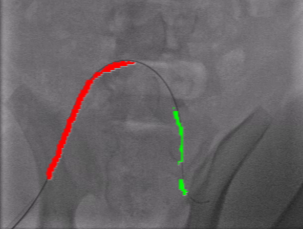

Qualitative Results. Fig. 5 illustrates the catheter and guidewire segmentation results of fine-tuning ViT on our method and different foundation models. The visualization portrays that our method excels in accurately delineating the catheter and guidewire structures, showcasing superior segmentation performance compared to other approaches. This figure further confirms that we can successfully train a federated endovascular foundation model without collecting users’ data and the trained foundation model is useful for the downstream segmentation task.

|

Animal |

Phantom |

Simulation |

Input

Ground Truth

LVM-Med

SAM

CLIP

Ours